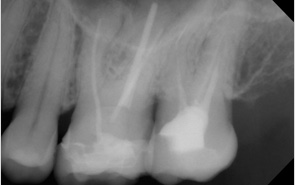

Weil es bei der Wurzelbehandlung um sehr kleine Größenverhältnisse geht, hat sich das Dentalmikroskop als Hilfsmittel durchgesetzt. Dies bedeutet, das die gesamte Wurzelbehandlung durch den ausgebildeten Spezialisten bei 10 - 30 facher optischer Vergrößerung durchgeführt wird. Zusätzlich kommt eine spezielle Beleuchtung zum Einsatz.

- Das Dentalmikroskop macht Wurzelkanäle für den Zahnarzt sichtbar, die ohne Mikroskop nicht zu sehen und deshalb auch nicht zu behandeln sind.